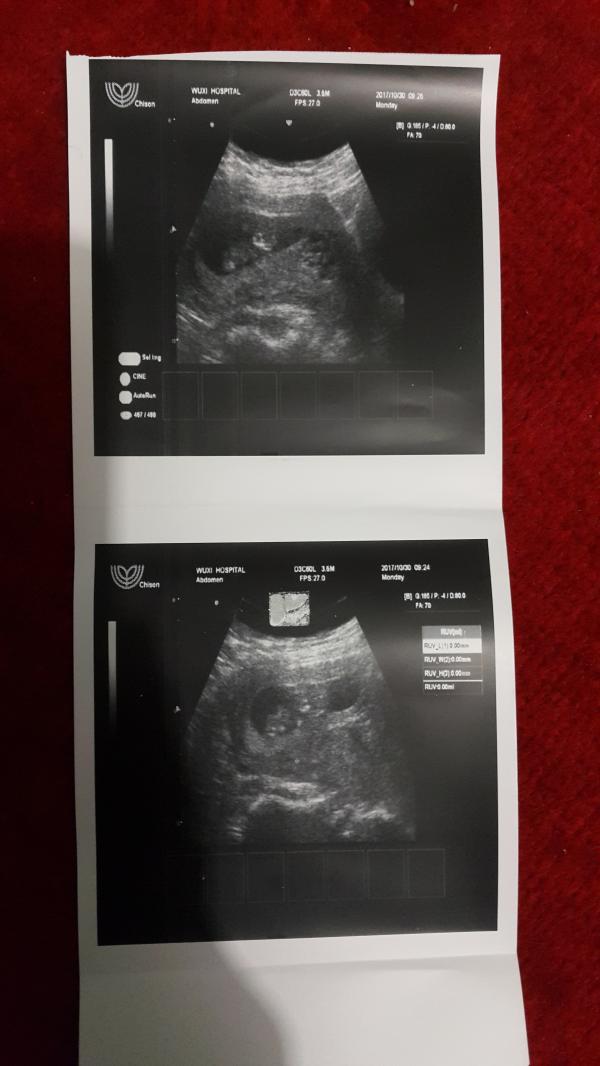

🔴🔴🔴Девочки всем привет удачного дня 🤗😙 хотела узнать есть тут гинекологи? Кто нибудь может сказать есть ли на этом фото гемотома??? Или я слепая или не туда смотрю 😄 я не вижу ее....